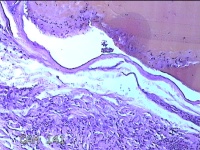

左侧中指皮下结节

性别

女

年龄

32岁

临床诊断

皮下结节

一般病史

发现左侧中指皮下结节1年余。

标本名称

大体所见

灰白暗红色肿物0.5x0.3x0.2cm两个,表面糜烂。